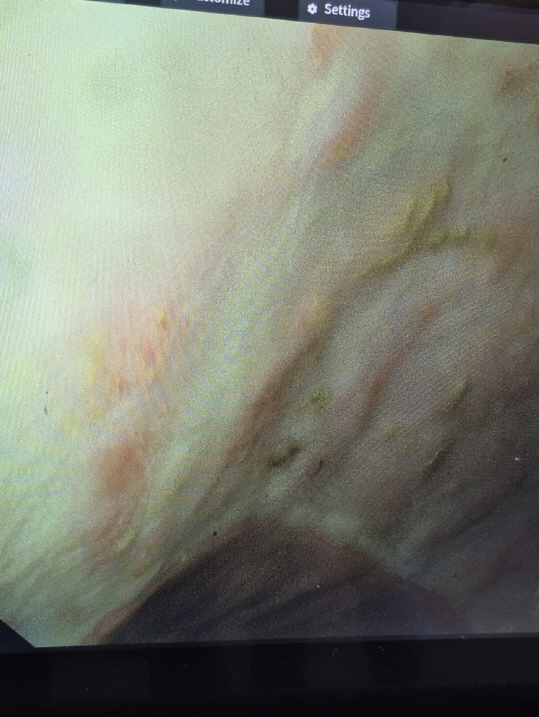

Ein flexibles Endoskop wird in die Nüstern des stehenden Pferdes eingeführt, bis zum Kehlkopf vorgeschoben und dann vom Pferd abgeschluckt. Über die Speiseröhre gelangt man in den Magen. Mithilfe von Luft wird der Magen aufgeweitet, sodass die Magenschleimhaut gut betrachtet und abgebildet werden kann. Außerdem kann man von auffälligen Lokalisationen Proben entnehmen.